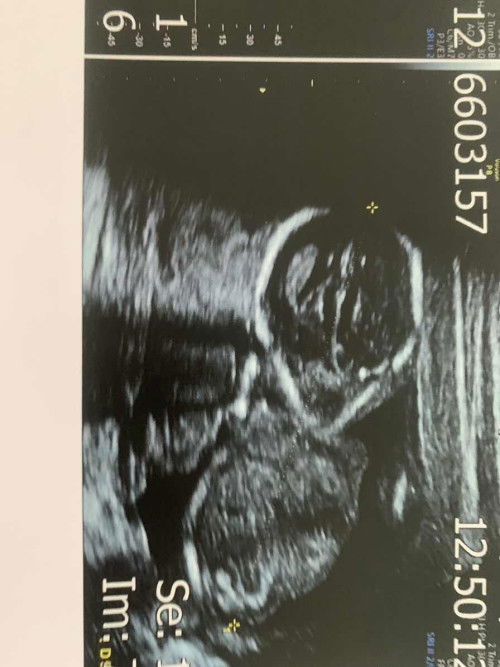

ขอดูภาพซาวด์ของแม่ๆหน่อยค่า 🥰

แม่ๆอัลตราซาวด์ตอน16 วีค ภาพน้องเป็นยังไงบ้างคะ แล้วน้องน้ำหนักเท่าไหร่กันบ้าง ☺️ บ้านนี้ไปซาวด์มาตอน 16วีค5วัน น้องหันหน้ามาให้ดู นึกว่าเอเลี่ยนเลยค่า 😂 น้องหนัก177กรัม ถือว่าปกติมั้ยคะแม่ๆ#ขอบคุณสำหรับคำตอบค่ะ